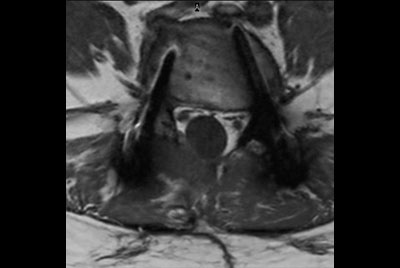

Push-button Lumbar Spine exam, under 5 minutes